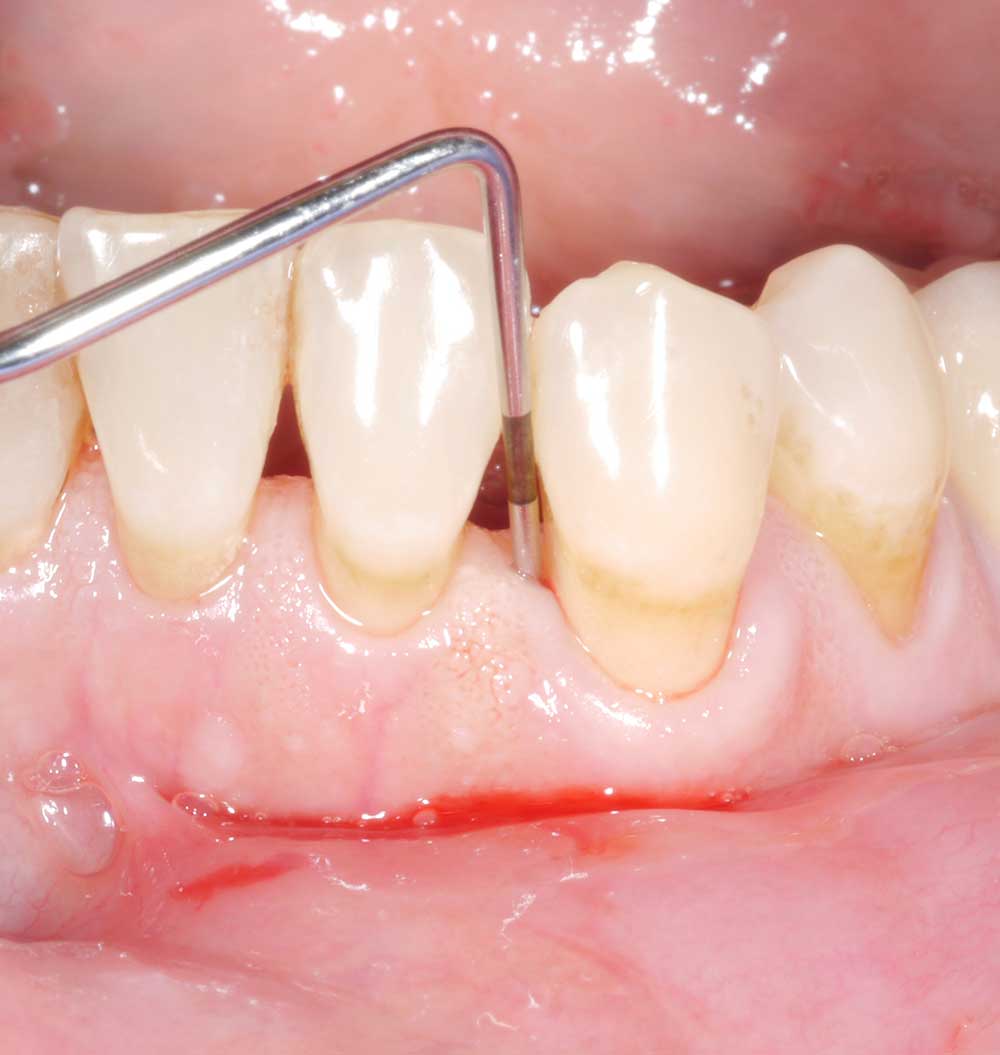

Zur zweiten Frage: Man kann beide Sondentypen verwenden, sowohl die Metall- als auch die Plastiksonde! Je nach prothetischer Versorgung kann die Plastiksonde aber gewisse Vorteile aufweisen. Durch die leichte Biegsamkeit der Plastiksonde erzielt man in gewissen Fällen (z.B. bei weit ausladenden Kronenformen oder bei Implantat getragenen Komplett-Kiefer-Versorgungen) einen besseren Zugang und dadurch vermutlich exaktere Messungen. Die Abbildung zeigt einen solchen Patientenfall mit einer Implantat getragenen Komplett-Kiefer-Versorgung (a). Bei den Abbildungen (b) und (c) zeigen sich deutliche Unterschiede je nachdem welcher Sondentyp verwendet wurde; während das Sondieren mit der Metallsonde 3mm ergab (b), zeigte sich ein deutlich höherer Messwert mit der Plastiksonde (c) – 8mm! Nach Abnahme der prothetischen Versorgung auf den Abbildung (d) und (e) sondiert man mit beiden Sonden gleich tief – ca. 10mm. Somit sollte man in der Klinik bedenken, dass je nach Zugang und prothetischer Versorgung die Plastiksonde eventuell aufgrund der leichten Biegsamkeit einen besseren Zugang und somit genauere Messung erzielen kann.